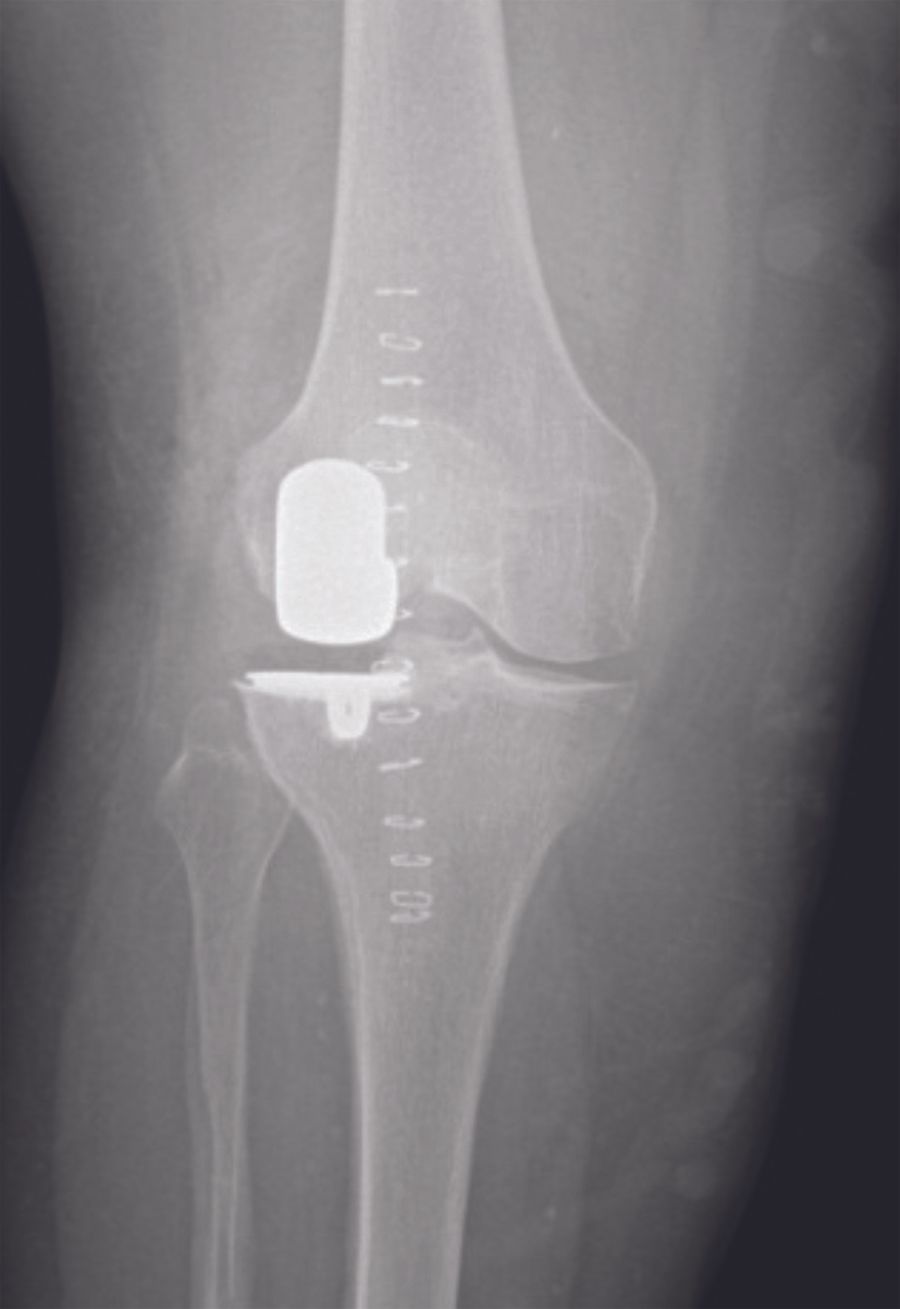

Radiographic assessment (fig. 1A-C)

My routine radiographic examinations of patients referred with pain believed to origin from knee OA include weight-bearing AP, lateral, and skyline views. These may be supplemented by valgus and varus stress radiographs, a Rosenberg view and / or MRI of the knee as needed. It is fundamental to establish bone-on-bone OA in the lateral compartment. Due to the specific features of lateral compartment OA bone-on-bone may not present on the weight-bearing radiograph with the knee extended. If there is any doubt about the bone-on-bone diagnosis in the lateral compartment supplemental imaging should be applied. On the weight-bearing AP view it is also assessed if there is preserved cartilage in the medial compartment. If in doubt a varus-stress radiograph may be helpful to assess this, and at the same time a varus stress will show correction of valgus deformity, opening of the lateral compartment, and indirectly that the LCL is functionally intact. In the lateral radiographic view the relative position of the femur and tibia should be assessed. If the femur is very posteriorly positioned it may be a sign that the ACL is degenerative and torn. The skyline view is specifically assessed for the presence of severe bone-on –bone OA. In general I only find MRI examination necessary in younger patients, particularly if the knee hos posttraumatic OA, in which case MRI can give good information about cartilage damage and degeneration in the lateral and the remaining compartments, as well as the status of cruciate ligaments.

- Final implantation (fig. 12)